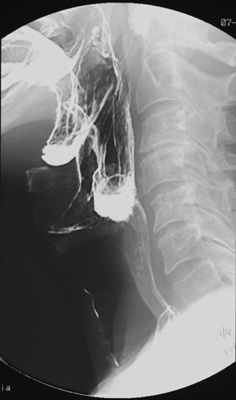

Lateral view of the barium-coated posterior pharynx and hypopharynx obtained during phonation demonstrates normal anatomy but also aspiration of barium into the larynx and trachea.